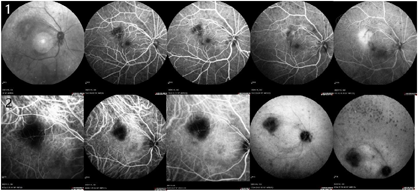

右眼裸眼视力0.5,矫正无提高;左眼裸眼视力1.0;右眼眼压18.2 mmHg,左眼眼压13.5 mmHg。双眼第一眼位正位,各方向运动无受限,右眼结膜充血,角膜KP(++),前房深、房水清,瞳孔圆,直径约3 mm,直间接对光反射存,晶体轻度混浊,玻璃体混浊,见细胞(+),眼底视盘界清,色淡红,C/D约0.3,颞上血管弓处见一黄白色绒球样病灶,位于视网膜下,邻近血管白鞘,后极部视网膜平伏;左眼结膜无充血,角膜透明,前房深、房水清,瞳孔圆,直径约3mm,直间接对光反射存在,晶体轻度混浊,玻璃体絮状混浊,眼底视盘界清,色淡红,C/D约0.3,黄斑中心凹反光未见,后极部视网膜平伏。眼底彩照示:右眼黄斑颞上方可见黄白色病灶(图1),光学相干断层扫描(optical coherence tomography,OCT)示病灶处视网膜内层结构破坏,下方脉络膜局限性增厚(图2)。荧光抗体(Fluorescent Antibody,FA)示病灶处早期呈低荧光,晚期渗漏(图3)。吲哚菁绿血管造影(indocyanine green angiography,ICGA)示病灶处始终呈低荧光(图3)。FA及ICGA晚期中周部和周边部网膜均可见广泛的点片状低荧光病灶(图3)。

临床上,获得性OT以玻璃体炎伴坏死性视网膜脉络膜炎为主,易误诊。本例患者眼底表现为黄斑颞上方黄白色绒球样病灶,需考虑与如细菌性及真菌性眼内炎、梅毒性葡萄膜炎、结核性葡萄膜炎、巨细胞病毒视网膜炎、急性视网膜坏死、眼弓蛔虫病等均可表现为坏死性视网膜脉络膜炎的疾病相鉴别,如细菌性及真菌性眼内炎起初也可表现眼底脉络膜白色病变,并迅速进展累及视网膜和玻璃体,OT进展相较而言更缓慢;梅毒性葡萄膜炎可有大片视网膜坏死,结核性葡萄膜炎可出现脉络膜视网膜疤痕,对于缺乏潜在感染的免疫学证据、缺乏特征性表现的情况,鉴别往往依赖于侵入性检测;急性视网膜坏死表现为广泛的视网膜周边白色坏死灶,而OT主要表现为局限性视网膜坏死;巨细胞病毒视网膜炎可有局限性脉络膜视网膜病变,但玻璃体炎症往往较轻,多表现为后极部视网膜坏死灶伴出血;眼弓蛔虫病也可表现为眼底白色坏死病灶,且与OT两者均常单侧发病,但眼弓蛔虫病常有典型的眼底肉芽肿性病变[7]。OT的诊断主要依据临床表现推定,但其临床表现的多样性以及与其他感染性、非感染性和肿瘤性疾病特征的重叠使得其诊断仍较为困难。OT是一种自限性疾病,部分OT即使用不适当的治疗也能恢复,由此,许多不典型的OT表现可能没有被正确诊断,且OT仍可引起部分患者严重、不可逆性视功能损害。因此,结合相关病史、影像学检查以及实验室检测确定诊断显得尤为重要[8]。首先,本例患者有明确的家养猫接触史。其次,该患者眼底的黄白色活动性病灶在OCT上呈现OT病灶典型的视网膜内层异常高反射以及视网膜全层反射紊乱(涂抹效应)[9],眼底血管造影检查也符合视网膜脉络膜炎的表现。此外,随着实验室检测技术的进步,通过检测眼内液和血清中弓形虫IgG与总IgG,计算出Goldmann-Witmer系数(goldmann-witmer coeifficient,GWC)已被认为是确诊OT诊断的金标准[10]。GWC>4可确诊OT,2~4提示OT可能。联合分析房水和血清的抗弓形体抗体水平和寄生DNA可以在90%诊断特异性的基础上,实现60%~70%的诊断敏感性[11]。本病例患者眼内液弓形虫IgG抗体56.74 IU/ml,血清总IgG 4680 IU/ml,弓形虫GWC>4,达到临床确诊标准。